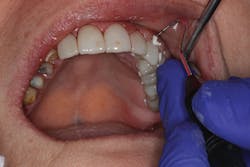

TheraCem exhibits minimal resistance to seating, but is not runny (figure 3). Cleanup is easy with hand instruments and floss (figure 4). For deeper subgingival margins, this cement is kind to the gingiva, although the margins should be thoroughly inspected to ensure complete removal of excess cement (figure 5).

Figure 3: TheraCem in use